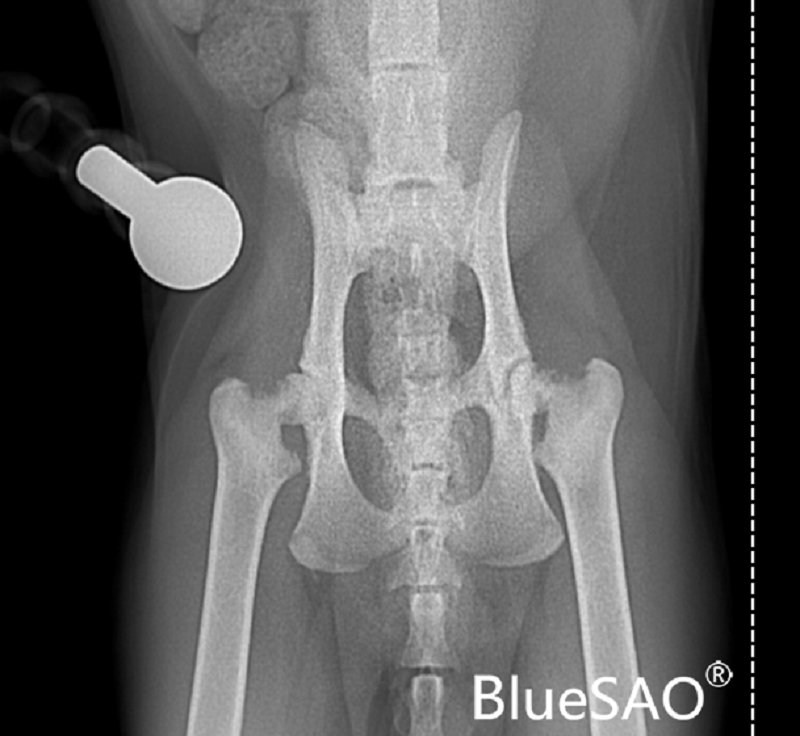

最近一年主人觉得猫咪性格越来越差,容易发怒咬人,不爱运动,长期趴卧,而且不让触摸后驱,以为是因为小时候送去医院去做手术导致动物敏感,屡次想带去医院检查,但是因为猫咪异常敏感,可能导致应激加剧而放弃,后来诱骗到纸箱后来带医院实施麻醉后检查。触诊可见明显后肢髋关节明显摩擦音,随后拍摄dr显示,双侧后肢出现明显的骨骺滑脱。和主人沟通后决定实施THR手术,先实施左侧更加敏感的患肢,一个月后置换另外一只患肢。

术前X光片:

术前拍摄骨盆正位、骨盆侧位、股骨正位和股骨侧位四张X光片。